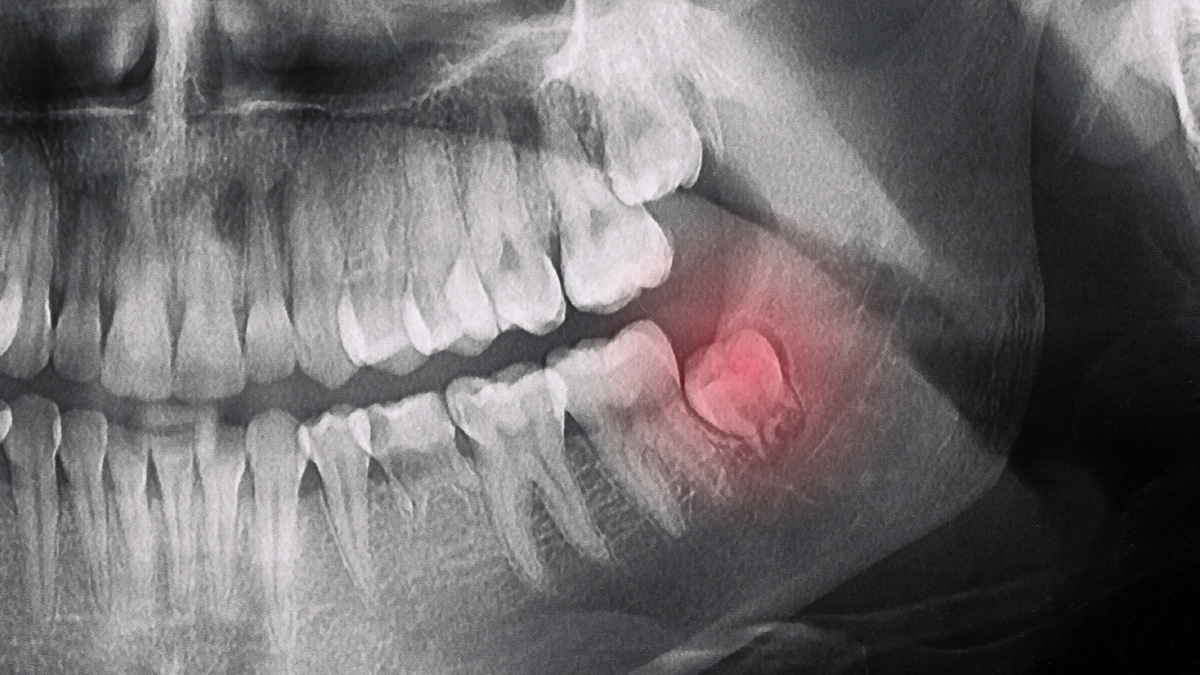

Horizontale Position (horizontaler retinierter Zahn)

Ein Weisheitszahn ist vollständig im Kieferknochen verankert und drückt typischerweise gegen die Wurzel eines Nachbarzahns. Die Zahnkrone ist horizontal zur Wurzel des Nachbarzahns oder zum Zahnfleischrand ausgerichtet. In diesem Fall ist der normale vertikale Durchbruchsweg des Zahns vollständig blockiert, sodass er nicht durchbrechen kann. Ein horizontal positionierter Zahn kann die Wurzeln benachbarter Zähne schädigen und Schmerzen und Infektionen verursachen. Außerdem führt er mit der Zeit zu Zahnfehlstellungen. Ein Weisheitszahn muss möglicherweise operativ entfernt werden, bevor er Probleme verursachen kann.

Während der Entwicklung erscheinen Weisheitszähne zunächst im Kindesalter als Knospen im Kieferknochen. Im Alter zwischen 17 und 25 Jahren nehmen sie beim Durchbruch zunächst eine mesioanguläre Position ein und versuchen allmählich, wieder in eine vertikale Position zurückzukehren. Aufgrund von Platzmangel und dem Vorhandensein benachbarter Zähne brechen Weisheitszähne, die sich nicht in eine vertikale Position bewegen können, jedoch schräg zu den Nachbarzähnen durch und bleiben im Kieferknochen verlagert. Die Zahnkrone ist nach vorne geneigt, was bedeutet, dass sie möglicherweise nicht vollständig durchbricht oder Druck auf den Nachbarzahn ausübt.

Dieser Druck auf den Nachbarzahn kann Karies, Wurzelresorption, Schmerzen, Zahnengstand, Infektionen und sogar Schmerzen verursachen. Die chirurgische Entfernung von Zähnen in dieser Position schützt den Nachbarzahn und beugt weiteren potenziellen Problemen vor.